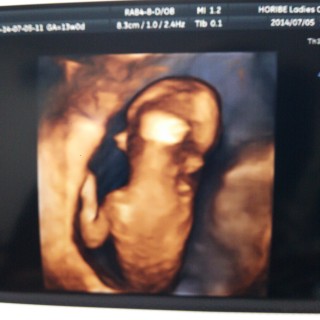

エコーをあてると、激しく動いていて、中々綺麗に撮れなくて、 先生が苦労されてやっと撮れた奇跡の1枚です。 ニッコリ笑っていて、嬉しさ倍増です。 身長約8.1センチ。

妊娠してる事に気づかず生理不順かな?って思って病院に行ったら初妊娠で13週目と言われビックリしました(>_<) 先生に凄く元気がいいですね^ ^って言ってもらったりエコー動画見たらなんだか嬉しくなりました^ ^ もっと早くに気づいたらよかった( ; ; ) 彼氏も大喜びでこれから大っきくなっていくのが楽しみです☆

CRL7.08㎝でした。